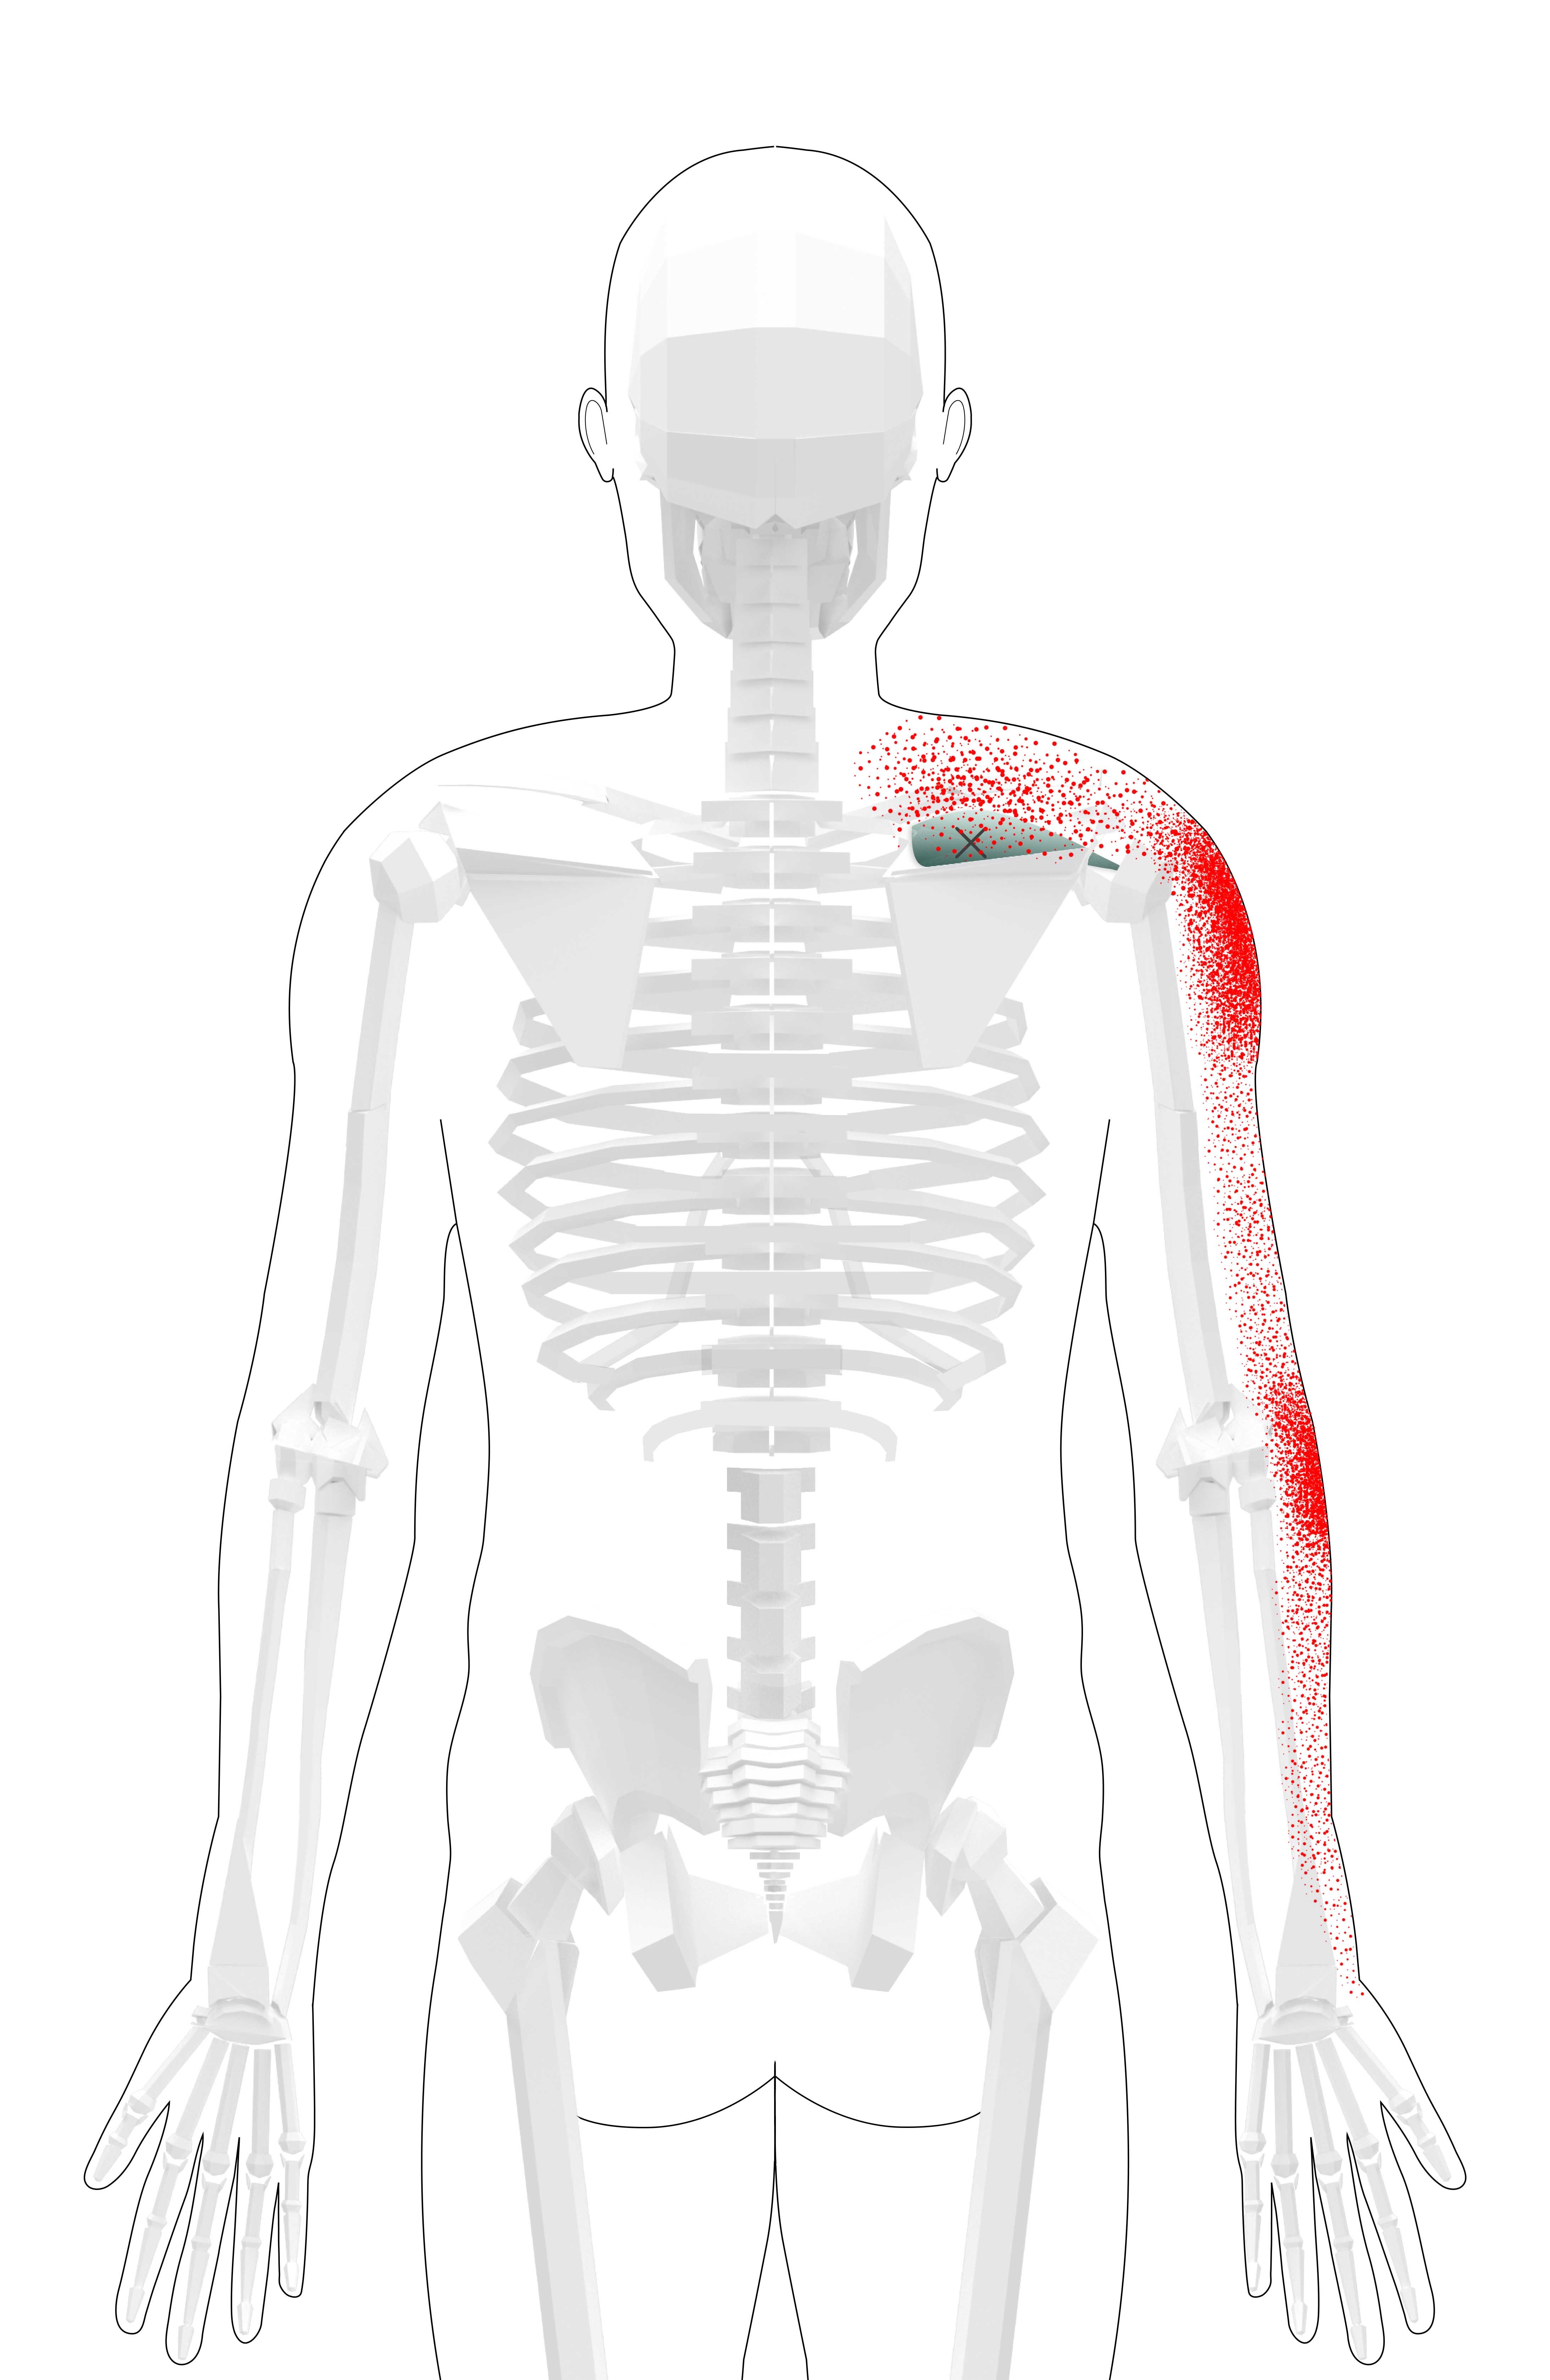

Supraspinatus Pain Referral Pattern

Supraspinatus Pain Referral Pattern - Web trigger point injections (tis) are commonly used as a treatment option in patients with acute and chronic muscle pains associated with an irritable, tight or taut muscle band, or palpable knot within a muscle that can radiate pain into specific distant or referred pattern called the “reference pain zone.” Web knowledge of anatomy, pain referral patterns, shoulder kinematics, and examination techniques are invaluable to the clinician in making an appropriate diagnosis and guiding treatment. Web results pressure pain sensitivity of the deltoideus, supraspinatus, and subscapularis muscles in the affected limb was lower than in the unaffected limb (p = 0.027, p = 0.005, p < 0.001). From the shoulder workshop @thebattleaxegym miami solving the symptomatic supraspinatus impingement we matched the subjective referral point to the palpation. Web supraspinatus tendonitis is a common cause of shoulder pain in athletes whose sports involve throwing and overhead motions. But you also might feel an ache in more distant, seemingly unrelated areas.

Supraspinatus is the most superior of the four rotator cuff muscles. Weaker version of the biceps pain pattern with the addition of pain at the base of the thumb. This pain pattern will occasionally include a forearm component as well. Web anterior aspect of the shoulder and down the length of the muscle to the elbow. Web in patients with shoulder pain, mtrps in the infraspinatus, supraspinatus, teres minor or subscapularis muscle, for example, may cause local and referred pain, which can be felt deep within the shoulder.

It originates from the medial aspect of the supraspinous fossa, a concave depression located above the spine of the scapula. Web trigger point referred pain patterns. Web referred pain patterns from supraspinatus (a), infraspinatus (b) subscapularis (c), pectoralis major (d), and biceps brachii (e) muscle trps as described by simons et al. Web supraspinatus tendinopathy is a common and disabling condition that becomes more prevalent after middle age [1] [2] and is a common cause of shoulder pain [3] [4]. Weaker version of the biceps pain pattern with the addition of pain at the base of the thumb.

This pain pattern will occasionally include a forearm component as well. A brief overview of the supraspinatus muscle, including anatomy, biomechanics, trigger point formation, and common referred pain maps. Web referred pain patterns from supraspinatus (a), infraspinatus (b) subscapularis (c), pectoralis major (d), and biceps brachii (e) muscle trps as described by simons et al. Web trigger point injections (tis).

A brief overview of the supraspinatus muscle, including anatomy, biomechanics, trigger point formation, and common referred pain maps. One of the most common symptoms of supraspinatus trigger points is referred pain. Web trigger point injections (tis) are commonly used as a treatment option in patients with acute and chronic muscle pains associated with an irritable, tight or taut muscle band,.

Web in patients with shoulder pain, mtrps in the infraspinatus, supraspinatus, teres minor or subscapularis muscle, for example, may cause local and referred pain, which can be felt deep within the shoulder. Web referred pain patterns of supraspinatus trigger points. A predisposing factor is resistive overuse [5]. When there is an injury at one site in the network it is.

Get help with supraspinatus video exercises and gain pain relief in just 30 seconds! From the shoulder workshop @thebattleaxegym miami solving the symptomatic supraspinatus impingement we matched the subjective referral point to the palpation. A predisposing factor is resistive overuse [5]. Identify the etiology of supraspinatus tendonitis. Web pain from the supraspinatus trigger points is referred to the outside of.

Pain patterns & symptoms if the supraspinatus contains active trigger points, you might experience local pain in the shoulder, right at these points. The most classic pain pattern is pain at the side of the shoulder. Lateral aspect of the shoulder and posterior arm and forearm; Web anterior aspect of the shoulder and down the length of the muscle to.

Supraspinatus Pain Referral Pattern - The most classic pain pattern is pain at the side of the shoulder. Web supraspinatus tendonitis is a common cause of shoulder pain in athletes whose sports involve throwing and overhead motions. Web referred pain patterns from supraspinatus (a), infraspinatus (b) subscapularis (c), pectoralis major (d), and biceps brachii (e) muscle trps as described by simons et al. Supraspinatus muscle pain symptoms and causes of trigger points. Web trigger point injections (tis) are commonly used as a treatment option in patients with acute and chronic muscle pains associated with an irritable, tight or taut muscle band, or palpable knot within a muscle that can radiate pain into specific distant or referred pattern called the “reference pain zone.” In my personal experience, the elbow referral on the lateral epicondyle is more prominent during release of the supraspinatus trigger points. Web 12k views 2 years ago. Complete disruption of muscle fibres Pain may progress into the dorsal aspect of the hand and fingers. Web anterior aspect of the shoulder and down the length of the muscle to the elbow.

The most classic pain pattern is pain at the side of the shoulder. Summarize the treatment and management options available for supraspinatus tendonitis. Web referred pain patterns of supraspinatus trigger points. Pain patterns & symptoms if the supraspinatus contains active trigger points, you might experience local pain in the shoulder, right at these points.